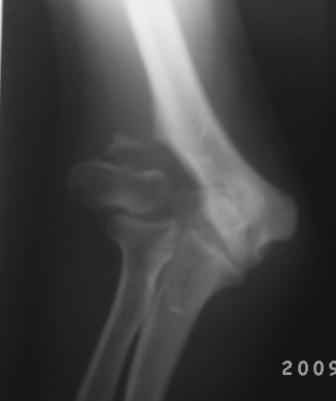

Уважаемые коллеги! Обратился больной 17 лет с жалобами на деформацию пр. локтевого сустава.

Травму получил 7 лет назад. Локально: вальгусная деформация л/с под углом 45гр., сгибание -30, разгибание-170гр., наружный мышелок плеча под пальцами подвижен, что интересно- мышелок плеча при пронации и супинации п/плечья вместе с головкой луча поднимается и опускается( см снимки).